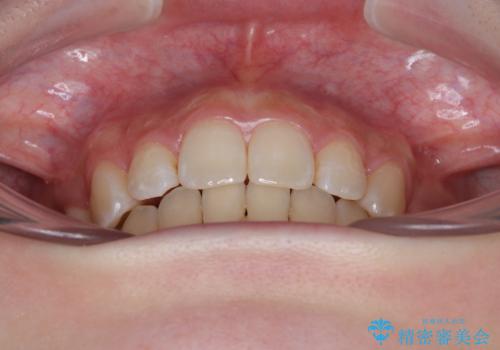

抜歯矯正により、下唇が前方に突出した感覚が大幅に改善されました。

- 上顎前歯の突出感を気にして来院された患者様です。

上下左右第一小臼歯4本を抜歯して、積極的に口元を引っ込めるよう、ワイヤー装置にて矯正治療を行うこととしました。